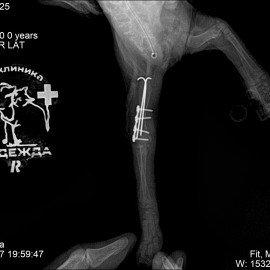

Был проведен осмотр и рентгенологическое исследование. Поставлен диагноз: перелом правой плечевой кости.

Была проведена операция: остеосинтез правого плеча.

Снимок 2 после операции.